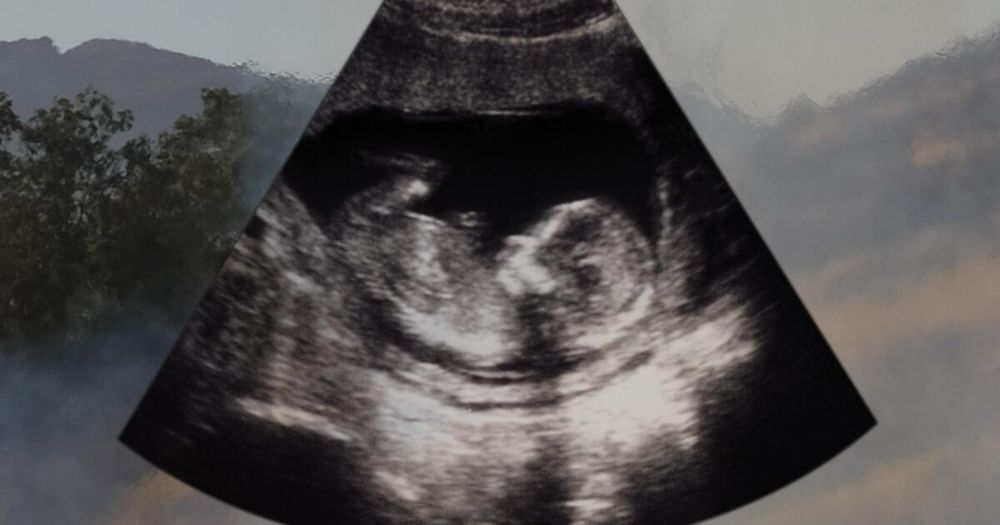

Should pregnant people evacuate L.A. to escape the smoke? Los Angeles' smoke levels pose unique risks to pregnant people and their fetuses. Here's what expectant parents should do to stay safe.

Pregnancy is a particularly sensitive period, & exposure to wildfire smoke may lead to smaller than average babies. Smoke isn’t the only concern, stress alone can alter physiological processes during pregnancy.

www.latimes.com/lifestyle/st...